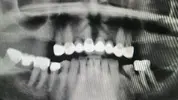

د. إنان أوزتورك طبيب أسنان

طب الأسنان